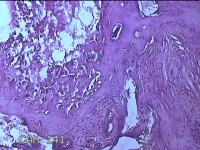

胎盘组织

性别

女

年龄

35岁

临床诊断

胎膜早破 早产

一般病史

停经36+1周,阴道流液3天。

标本名称

大体所见

灰白暗红色胎盘组织18x15.5x2.3㎝一个,表面光滑,血管清晰,颜色发暗,绒毛面结节状,轻度糜烂,表面有少许凝血块,切面见绒毛内有部分淤血,边缘蜕膜可见多个小血肿,脐带15x1.5x0.8㎝,切断脐带,见脐血管内有凝血块。